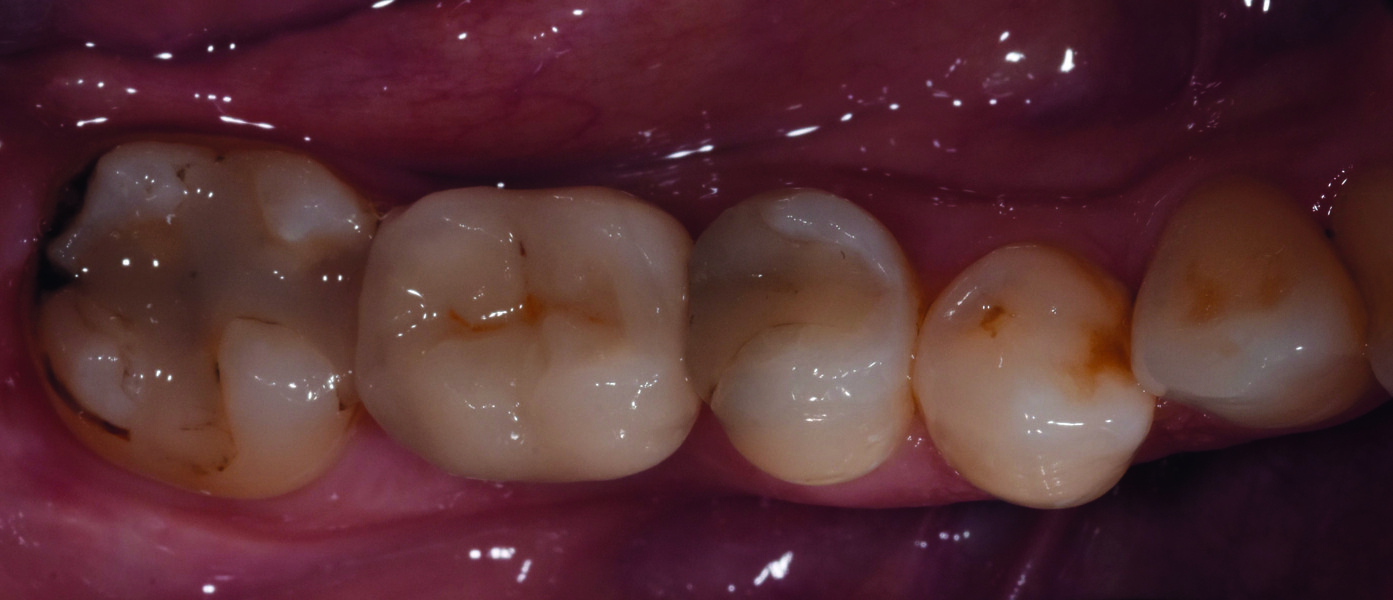

Jour de la pose de la couronne d’usage

Fig. 26 : Intégration de la couronne d’usage, avec vérification de l’occlusion, en vue vestibulaire.

Fig. 27 : Intégration de la couronne d’usage, en vue occlusale.